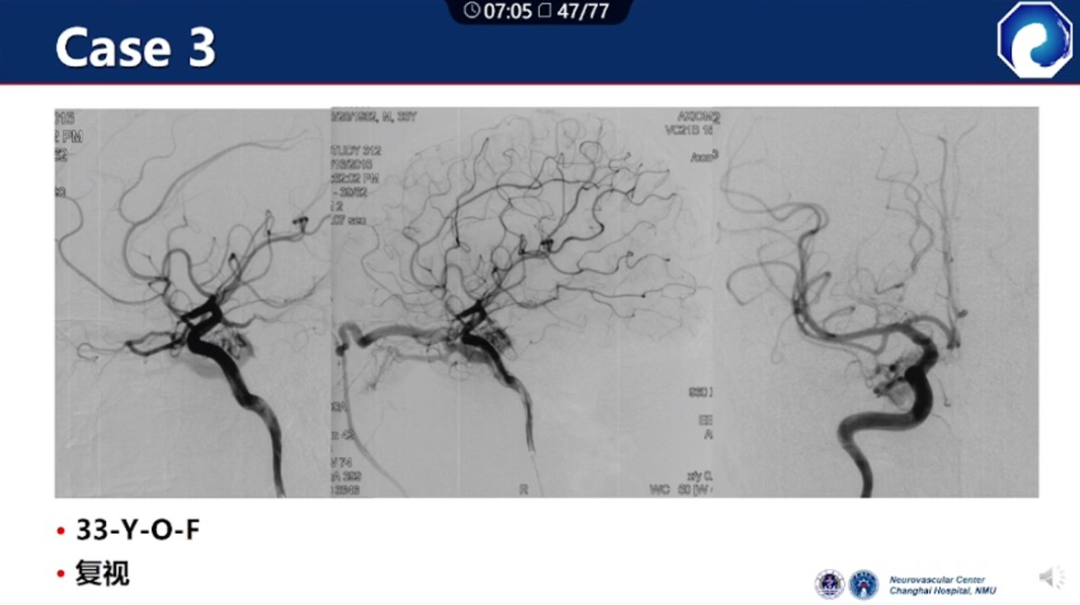

痿口静脉端的识别至关重要。

痿口静脉端精准完全闭塞是DAVF治愈的关键。